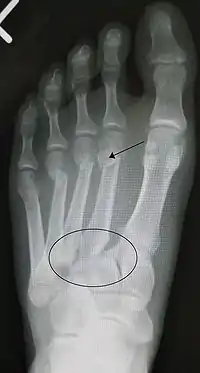

Fractura de lisfranc, marcada con el círculo. Además, doble fractura a nivel del 2º y 4º metatarsiano.

El diagnóstico se basa en la imagenología y la clínica, esta última se puede presentar con las características clásicas de una fractura (dolor, aumento de volumen e impotencia funcional) en la región media del pie, sumada a una equimosis en la región del arco plantar. La valoración radiográfica de las relaciones normales del complejo tarsometatarsiano se lleva a cabo en las proyecciones Dorsoplantar en la que la cortical medial de la cuña intermedia, se continua con la cortical medial de la base del 2º metatarsiano. En la proyección oblicua lateral: la cortical medial del cuboides se continua con la cortical medial de la base del 4º metatarsiano en las placas simples y de estrés.